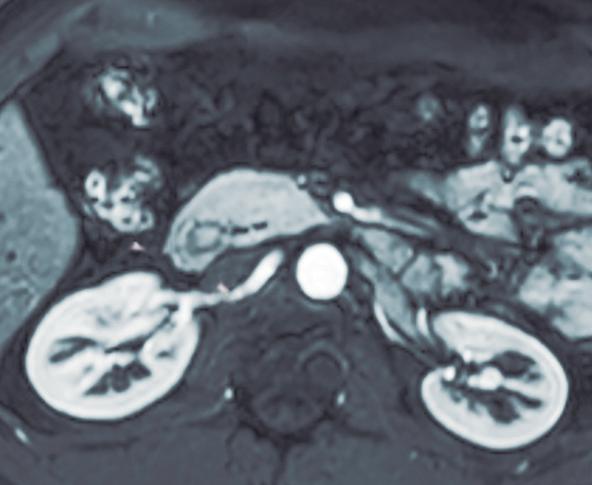

Páncreas Anular

Consiste en una anomalía de la migración del brote pancreático ventral, el cual no rota o lo hace de manera incompleta, resultando en la presencia de tejido glandular pancreático a la derecha del duodeno, rodeando a su 2° porción (Figura 8). Han sido descriptos dos subtipos: el extramural, donde el conducto de Wirsung rodea al duodeno uniéndose al conducto pancreático principal; y el intramural, donde el tejido pancreático se entremezcla con la pared duodenal y sus secreciones drenan directamente a la luz a través de conductos muy pequeños.16

En las imágenes encontramos parénquima pancreático rodeando a la 2° porción duodenal, habitualmente en toda su circunferencia y en ocasiones de manera incompleta. En la colangio-RM es posible visualizar al conducto pancreático a la derecha del duodeno, con un recorrido que se dirige a la ubicación de la papila mayor (Figura 9).17

A) Resonancia magnética secuencia T1 con gadolinio, plano axial. Las flechas señalan el parénquima del páncreas prolongado hacia la derecha “abrazando” a la 2° porción duodenal (cabeza de flecha). B) Resonancia magnética, secuencia T1 con gadolinio, plano axial, corte más caudal al previo. Las flechas nos muestran al páncreas rodeando de manera completa a la 2° porción del duodeno. C) Resonancia magnética, secuencia T2, plano coronal. La flecha señala presencia de parénquima glandular y conducto pancreático a la derecha del duodeno (cabezas de flecha). D) Resonancia magnética, secuencia T2, plano coronal, corte posterior al previo. El páncreas anular y su conducto de drenaje rodean en forma completa al duodeno (cabezas de flecha). E) Colangio-RM. El conducto del páncreas ventral (flechas) hace un giro, rodea al duodeno (cabeza de flecha) y se une al conducto pancreático principal para drenar en la papila mayor. F) Colangio-RM. La imagen magnificada muestra con mayor detalle el recorrido del conducto de Wirsung en el contexto de un páncreas anular.

El páncreas anular en neonatos, cuando es sintomático, provoca síndrome de obstrucción gástrica, clínicamente manifestado con vómitos como consecuencia de la compresión y estenosis de la 2° porción duodenal. En los adultos también puede originar obstrucción gastrointestinal, y los pacientes presentan dolor abdominal, habitualmente postprandial y/o vómitos. En menor medida puede predisponer a PAR o bien a

Más allá del diagnóstico de esta anomalía debemos buscar signos imagenológicos indirectos de obstrucción gastrointestinal, como son la dilatación gástrica y de la 1° porción duodenal (Figura 10), con estrechez de la luz del duodeno en el sitio por donde transcurre a través del páncreas anular.18,19

A) Tomografía computada con contraste, plano coronal. El páncreas anular (flecha) provoca dilatación de la 1° porción del duodeno (cabezas de flecha). B) Tomografía computada con contraste, plano axial. Flechas: páncreas anular. Cabeza de flecha: duodeno. C) Tomografía computada con contraste, plano axial, corte más caudal que el previo. Flechas: páncreas anular.

Figura 10. Páncreas anular con obstrucción del tracto de salida gastrointestinal